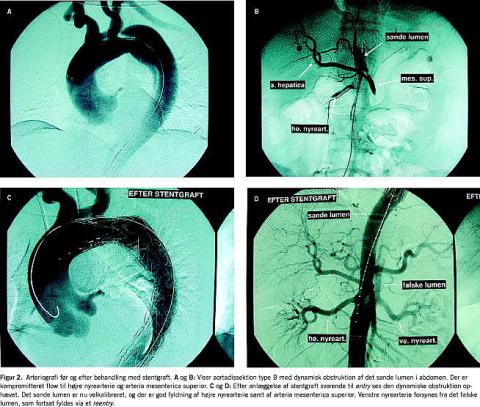

Figur 2 viser arteriografi før og efter stentgraftbehandling af type B-aortadissektion.

I 1999 blev endovaskulær behandling af B-dissektioner med stentgraftteknik beskrevet for første gang [14, 15]. Via

a. femoralis indføres en selvekspanderende stentgraft, så

den dækker det proksimale entry og dermed skaber trombose i det falske lumen, mens flowet i det sande lumen øges. Teknikken kan eventuelt suppleres med stentning af for eksempel viscerale arterier ved statisk obstruktion af disse.